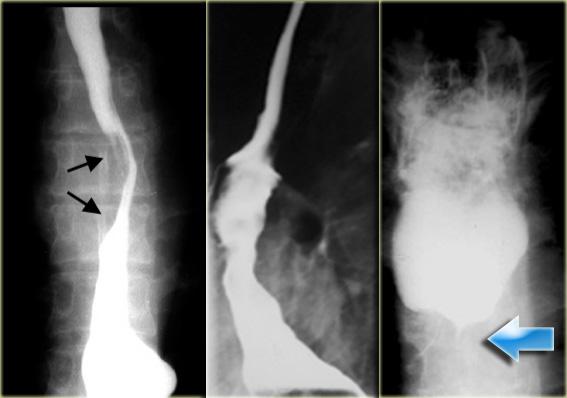

Bên trái là hình ảnh một bệnh nhân bị tụ máu thực quản.

Bệnh nhân nhập viện với triệu chứng đau ngực và khó nuốt sau khi nôn mửa.

Ngoài hình ảnh động mạch chủ ngoằn ngoèo, X-quang ngực bình thường.

Chụp thực quản barium cho thấy lòng thực quản hẹp (các mũi tên) trên phim thẳng và lòng thực quản dẹt trên phim nghiêng (các đầu mũi tên), gợi ý tụ máu trong thành thực quản.

Trên CT, chẩn đoán tụ máu trong thành thực quản được xác nhận.

Khối tụ máu thành thực quản tăng tỷ trọng (đầu mũi tên) được thấy cạnh ống thông mũi – dạ dày (mũi tên).

Sau điều trị bảo tồn, sáu tháng sau chụp thực quản barium cho kết quả bình thường.

Bên trái là hình ảnh một bệnh nhân có biến chứng sau nội soi phức tạp.

Can thiệp dụng cụ gây rách niêm mạc và tụ máu trong thành thực quản dạng bóc tách, tạo ra hình ảnh lòng đôi với dải niêm mạc phân tách (các mũi tên).

Ngoài cùng bên trái là hình ảnh thoát thuốc cản quang trong thành thực quản (mũi tên) sau nong đoạn xa điều trị co thắt tâm vị.

Ở giữa là hình ảnh thoát thuốc cản quang trong thành thực quản (mũi tên) sau nội soi phức tạp.

Bên phải là hình ảnh thủng thực quản sau sinh thiết với thuốc cản quang thoát ra ngoài lòng thực quản (mũi tên).